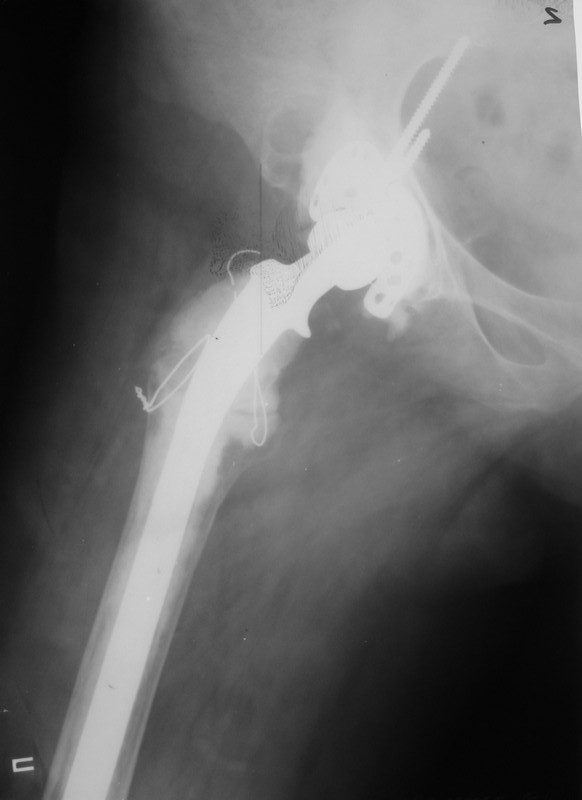

Уважаемые коллеги,в клинику поступила пациентка 51год с нестабильным антипротрузионным кольцом и вывихом эндопротеза.

В течени длительного времени у пациентки ревматойдный полиартрит с приемом преднизолона.В 1994году произведено эндопротезирование правого тазобедренного сустава бесцементным эндопротезом Biotronic.В 2000году по поводу нестабильности эндопротеза проведено ревизионное вмешательство-удаление чашки и ножки, некрэктомия.Установка антипротрузионного кольца, цементной чашки и ревизионной цементной ножки Beznoska.В 2007году выявлена клиникорентгенологическая картина нестабильности кольца.В 2008году пациентка упала, произошел вывих эндопротеза и дислокация кольца с переломом винтов.

Планируем ревизионное вмешательство-удаление кольца, чашки, винтов, пластика верхнего края вертлужной впадины массивным аллотрансплантатом с последующей установкойантипротрузионного кольца типа Burch-Shneider.